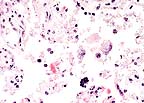

Higher magnification of the above field. The bluish haze within the cytoplasm of this trophoblast are numberous intracellular coccobacilli compatible with Coxiella burnetti. (HE, 400X, 21K)

Gram-negative coccobacilli compatible with Coxiella burnetti in the trphoblast of a 3-year-old gazelle (Brown-Hopps', 400X, 35K)

Significant lesions were limited to the placenta. Several epithelial cells in areas of necrosis have fuzzy blue cytoplasm. Sections were stained with Gimenez method, which revealed <1 micron diameter red organisms within the cytoplasm. Organisms did not stain with Brown-Brenn Gram stain. Paraffin blocks were submitted to Washington Animal Disease Diagnostic Laboratory for immunohistochemistry. Sections were positive for Coxiella and negative for Chlamydia.

Conference Note: Microscopically, placental trophoblasts lining the cotyledonary villi are distended by small, approximately 1æm diameter, basophilic, intracytoplasmic organisms. The differential diagnosis for intratrophoblastic organisms in cases of placentitis includes Coxiella, Brucella, Campylobacter, and Chlamydia. Of these, only Coxiella burnetii and Chlamydia stain positively with Gimenez or modified acid-fast stains. The morphology of the intracytoplasmic organisms on Gimenez-stained sections should differentiate C. burnetii from Chlamydia since C. burnetii appear as pleomorphic, or thin, rod-shaped structures, while chlamydial elementary bodies are uniformly small and round. Some, but not all, sections examined by conference participants had a focal vasculitis of one of the larger placental vessels.